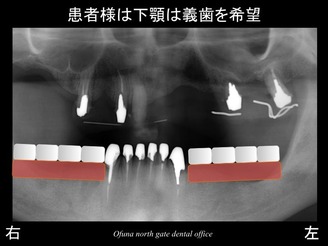

患者様は、上顎は義歯(入れ歯)ではない、固定式の治療をご希望されていました。

この場合、インプラント治療 と 天然歯でのブリッジ が考えられます。

以下のような治療法です。

上顎右側の3歯欠損には、3本のインプラントを埋入、

上顎右側の前歯は、ブリッジ、

上顎左側の前歯部には、3本のインプラントを埋入し4歯分を作製するブリッジ、

上顎の左側の奥歯は、天然歯のブリッジ

です。